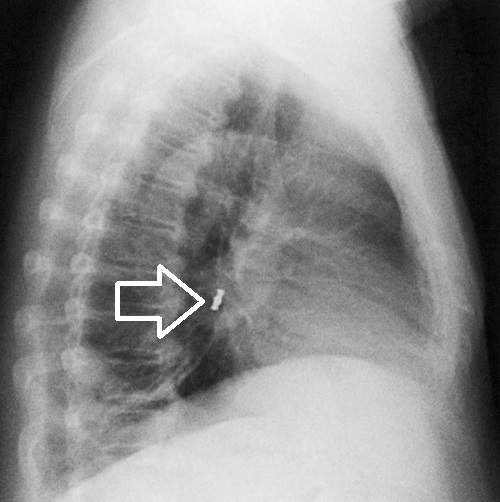

特に高齢者などで、食べている最中に差し歯、義歯、歯のかぶせ(歯冠)を知らずに飲み込んでしまい(誤嚥)、むせたり、咳き込むことがあります。人工歯が外れたのに気付かず、喉(のど)に引っ掛かる感じがするので、甲状腺の病気と勘違いする人もいます。しかし、人工歯は気管支まで落ちて、気管支異物になっています。

子供などでは、未発達な歯が体育の授業中に折れたり、抜けたりして気管支異物にる可能性があります。小学生の歯の外傷は水泳、体操、鉄棒の最中に起こりやすい。

気道異物は、

- 乳幼児と高齢者に多い

- 分岐角の小さい右側に多い

- Holzknecht sign ;縦隔が吸気時に患側へ、呼気時に健側へ偏位